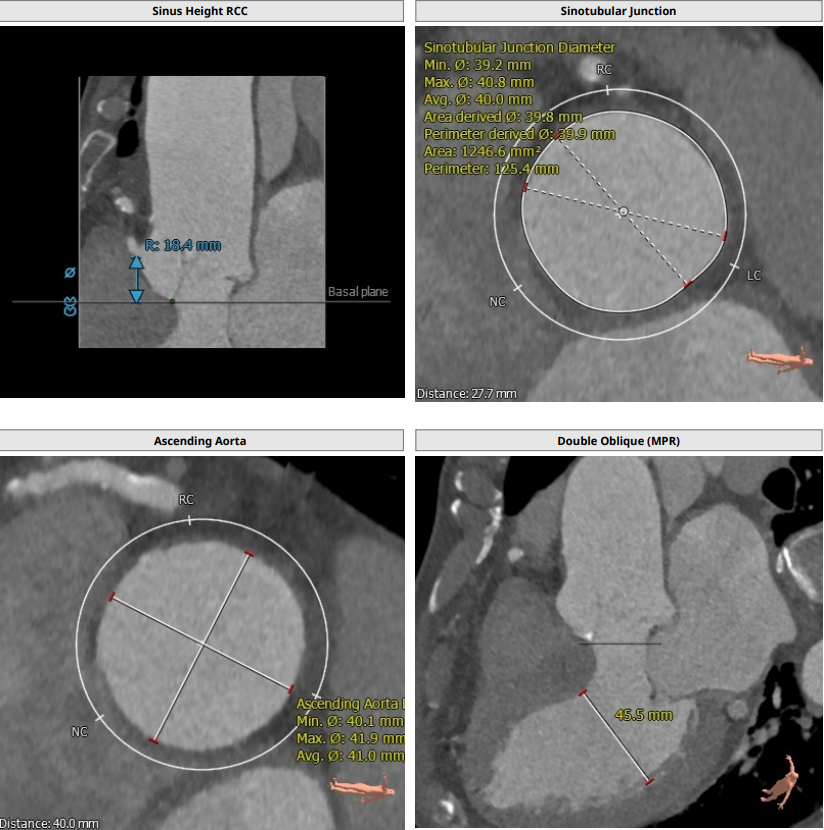

患者男,83岁,解剖为三叶瓣,瓣环径25.5,LVOT25,法式窦结构大,长短颈均超过43,左冠高度16.2,右冠高度18.4,STJ39.9,高度为27.7,升主动脉稍增宽,均径在40.1。

综合整体结构,决定选用VenusA29号瓣膜进行植入,VenusA29号瓣膜29MM的瓣环经相对于25.5的瓣环解剖,25的LVOT有13%以上的oversize,且STJ高度为39.9,升主为40.1,相对于VenusA29号瓣膜最大处44的特点,均可以提供锚定力。